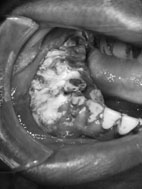

圖2. 第四期鱗狀細胞癌

主要是因口腔黏膜長期在內在及外在的因素刺激下產生細胞的變異,口腔癌在形成是多階段之變化,先由正常組織表面產生異常變異或增生,可形成潰瘍、白斑、紅斑及疣狀上皮增生等癌前期徵兆,因長期的發炎刺激和藥物食物的毒性反應造成細胞基因突變,轉變成癌細胞而形成口腔癌。口腔癌常見的部位以台灣病患來講,多數是在雙側頰黏膜、舌頭的側緣和牙齦,約佔罹癌病例的80%以上,其次會分佈於後臼齒區、上下唇、上腭的軟硬腭和口底,雙側頰黏膜的病例同時也會造成張口受限,導致進食困難。因為癌細胞的增生相當快,常會造成黏膜表面營養不足而形成潰瘍,潰瘍常為無痛卻不會好的傷口,通常初期罹癌大都是無症狀的,因癌症造成癌細胞快速生長,常會在短時間內變成大腫瘤,也因此常常受到忽略而延遲了治療的時機。